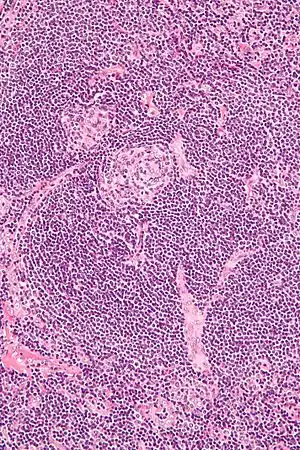

| Micrograph of Castleman disease showing hyaline vascular features including atrophic germinal center, expanded mantle zone, and a radially penetrating sclerotic blood vessel ("lollipop" sign). H&E stain. | |

- Hyaline vascular: regressed germinal centers, follicular dendritic cell prominence or dysplasia, hypervascularity in interfollicular regions, sclerotic vessels, prominent mantle zones with an "onion-skin" appearance.[13]